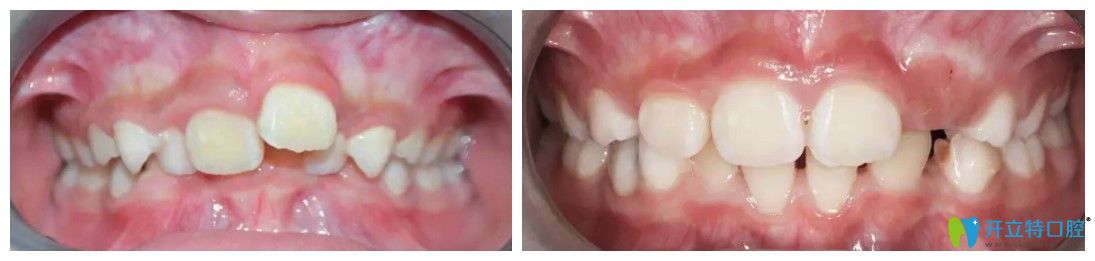

牙博士口腔兒童mrc牙齒矯正效果怎么樣?案例知曉

患者:西西

年齡:7歲

主治醫(yī)生:王聰

牙齒情況:替牙期牙列擁擠、前牙深覆合